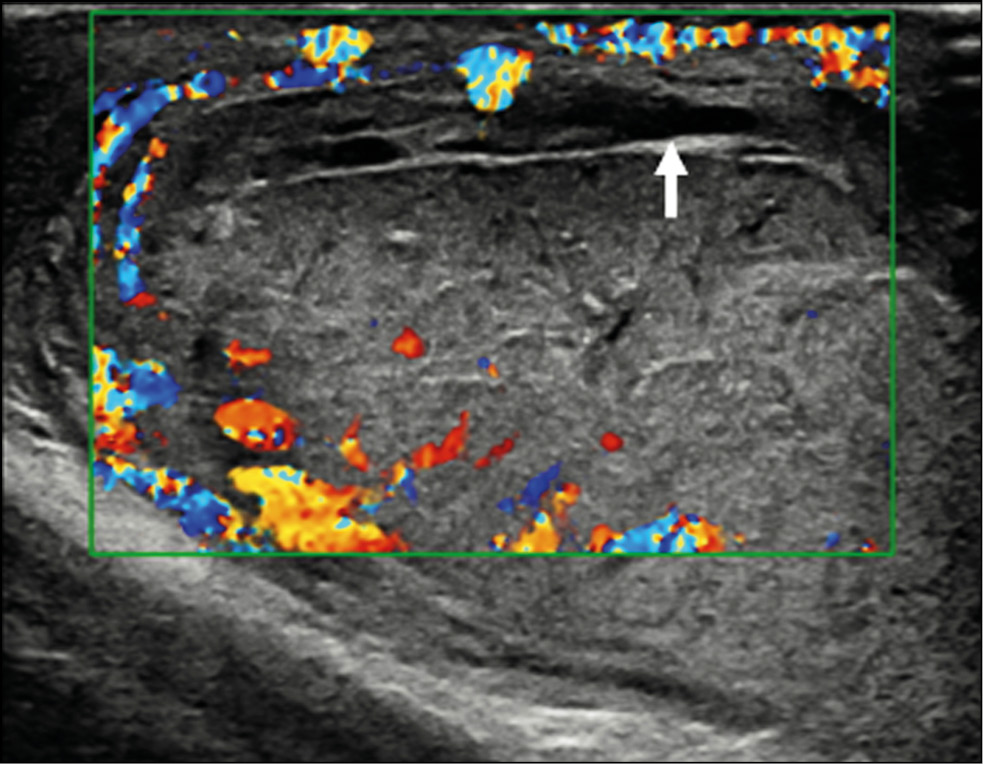

A healthy 15-year-old male teen was hit in the scrotum with a kick in the groin during a football match. He had an immediate and severe pain. After a few hours, although symptoms had improved, he presented to our emergency department with persistent swelling and purplish discoloration of the left scrotum. He did not report any other injuries. The genitourinary examination revealed that the left hemiscrotum was about two times larger than the right with severe ecchymosis. The left testicle was difficult to palpate because of pain and swelling, whereas the right testicle had a normal size and did not reveal any palpable abnormalities. The cremasteric reflex was not elicited on the left side. Scrotal ultrasonography (US) showed moderate scrotal edema and hematocele with a discontinuity in the tunica albuginea characterized by an abnormal contour (Figure 1). Color Doppler US (CDUS) documented a loss of vascularization in the upper pole that extruded into the broken portion of the testicle of approximately 2.5 cm (Figure 2) but no evidence of torsion or infarction. Urology consultation was requested, and a contrast-enhanced US (CEUS) was performed, which confirmed the diagnosis of testicular rupture and determined the amount of the vital parenchyma (Figure 3). The patient was hospitalized for urgent examination of the left hemiscotum based on the US results. During surgery, a large hematocele was evacuated, and a closer inspection of the testicle revealed a lesion of the tunica albuginea. Primary closure of the tunica was performed (Figure 4). The patient made an uneventful recovery, and he was discharged after 4 days.

Figure 3. Contrast-enhanced ultrasonography image determines the extent of vital parenchyma, helping in the preoperative decision-making process, and allows the recovery of vital testicular tissue, avoiding the need for orchidectomy.